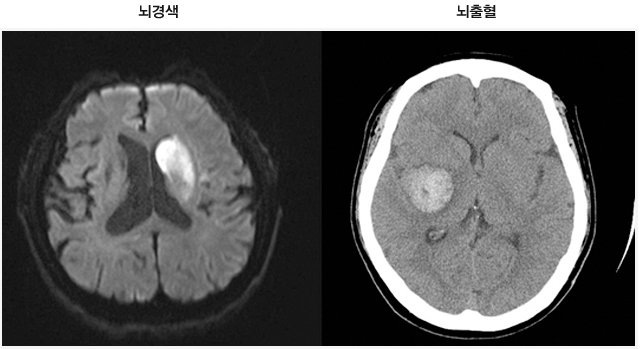

이 질병을 진단하는 검사로는 몇 가지가 이어질 수 있답니다. 뇌졸중에는 뇌출혈과 뇌경색이 있는데, 이 양쪽 모두는 양상이 다르며 무엇이냐에 따라서 치료 절차도 상이하기 때문에 뇌경색 검사방법으로 진단을 정확하게 받는 것이 선행되어야 하고 중요한 부분이라고 할 수 있어요. 우선 뇌경색 초기증상이 보인다면 방문을 하여서 전문가와 상담을 진행하게 되겠고, 진행되는 뇌경색 검사방법으로는 뇌혈관 자기 공명영상, 공명영상 촬영술, 전산화 단층 촬영, 심장 초음파, 경동맥 초음파, 뇌혈관 초음파 등의 방식으로 환자의 현재 상태를 파악하여 치료가 진행되겠죠.